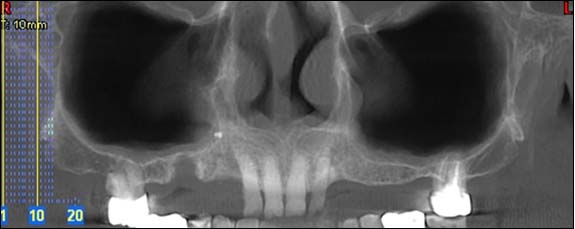

Dernière technologie à notre disposition, cette technique permet de voir en 3 dimensions des images de votre bouche et de mettre en évidence des pathologies ou des anomalies que les autres techniques ne permettent pas d'objectiver.

Coupe axiale

Reconstruction panoramique

Reconstruction coronale